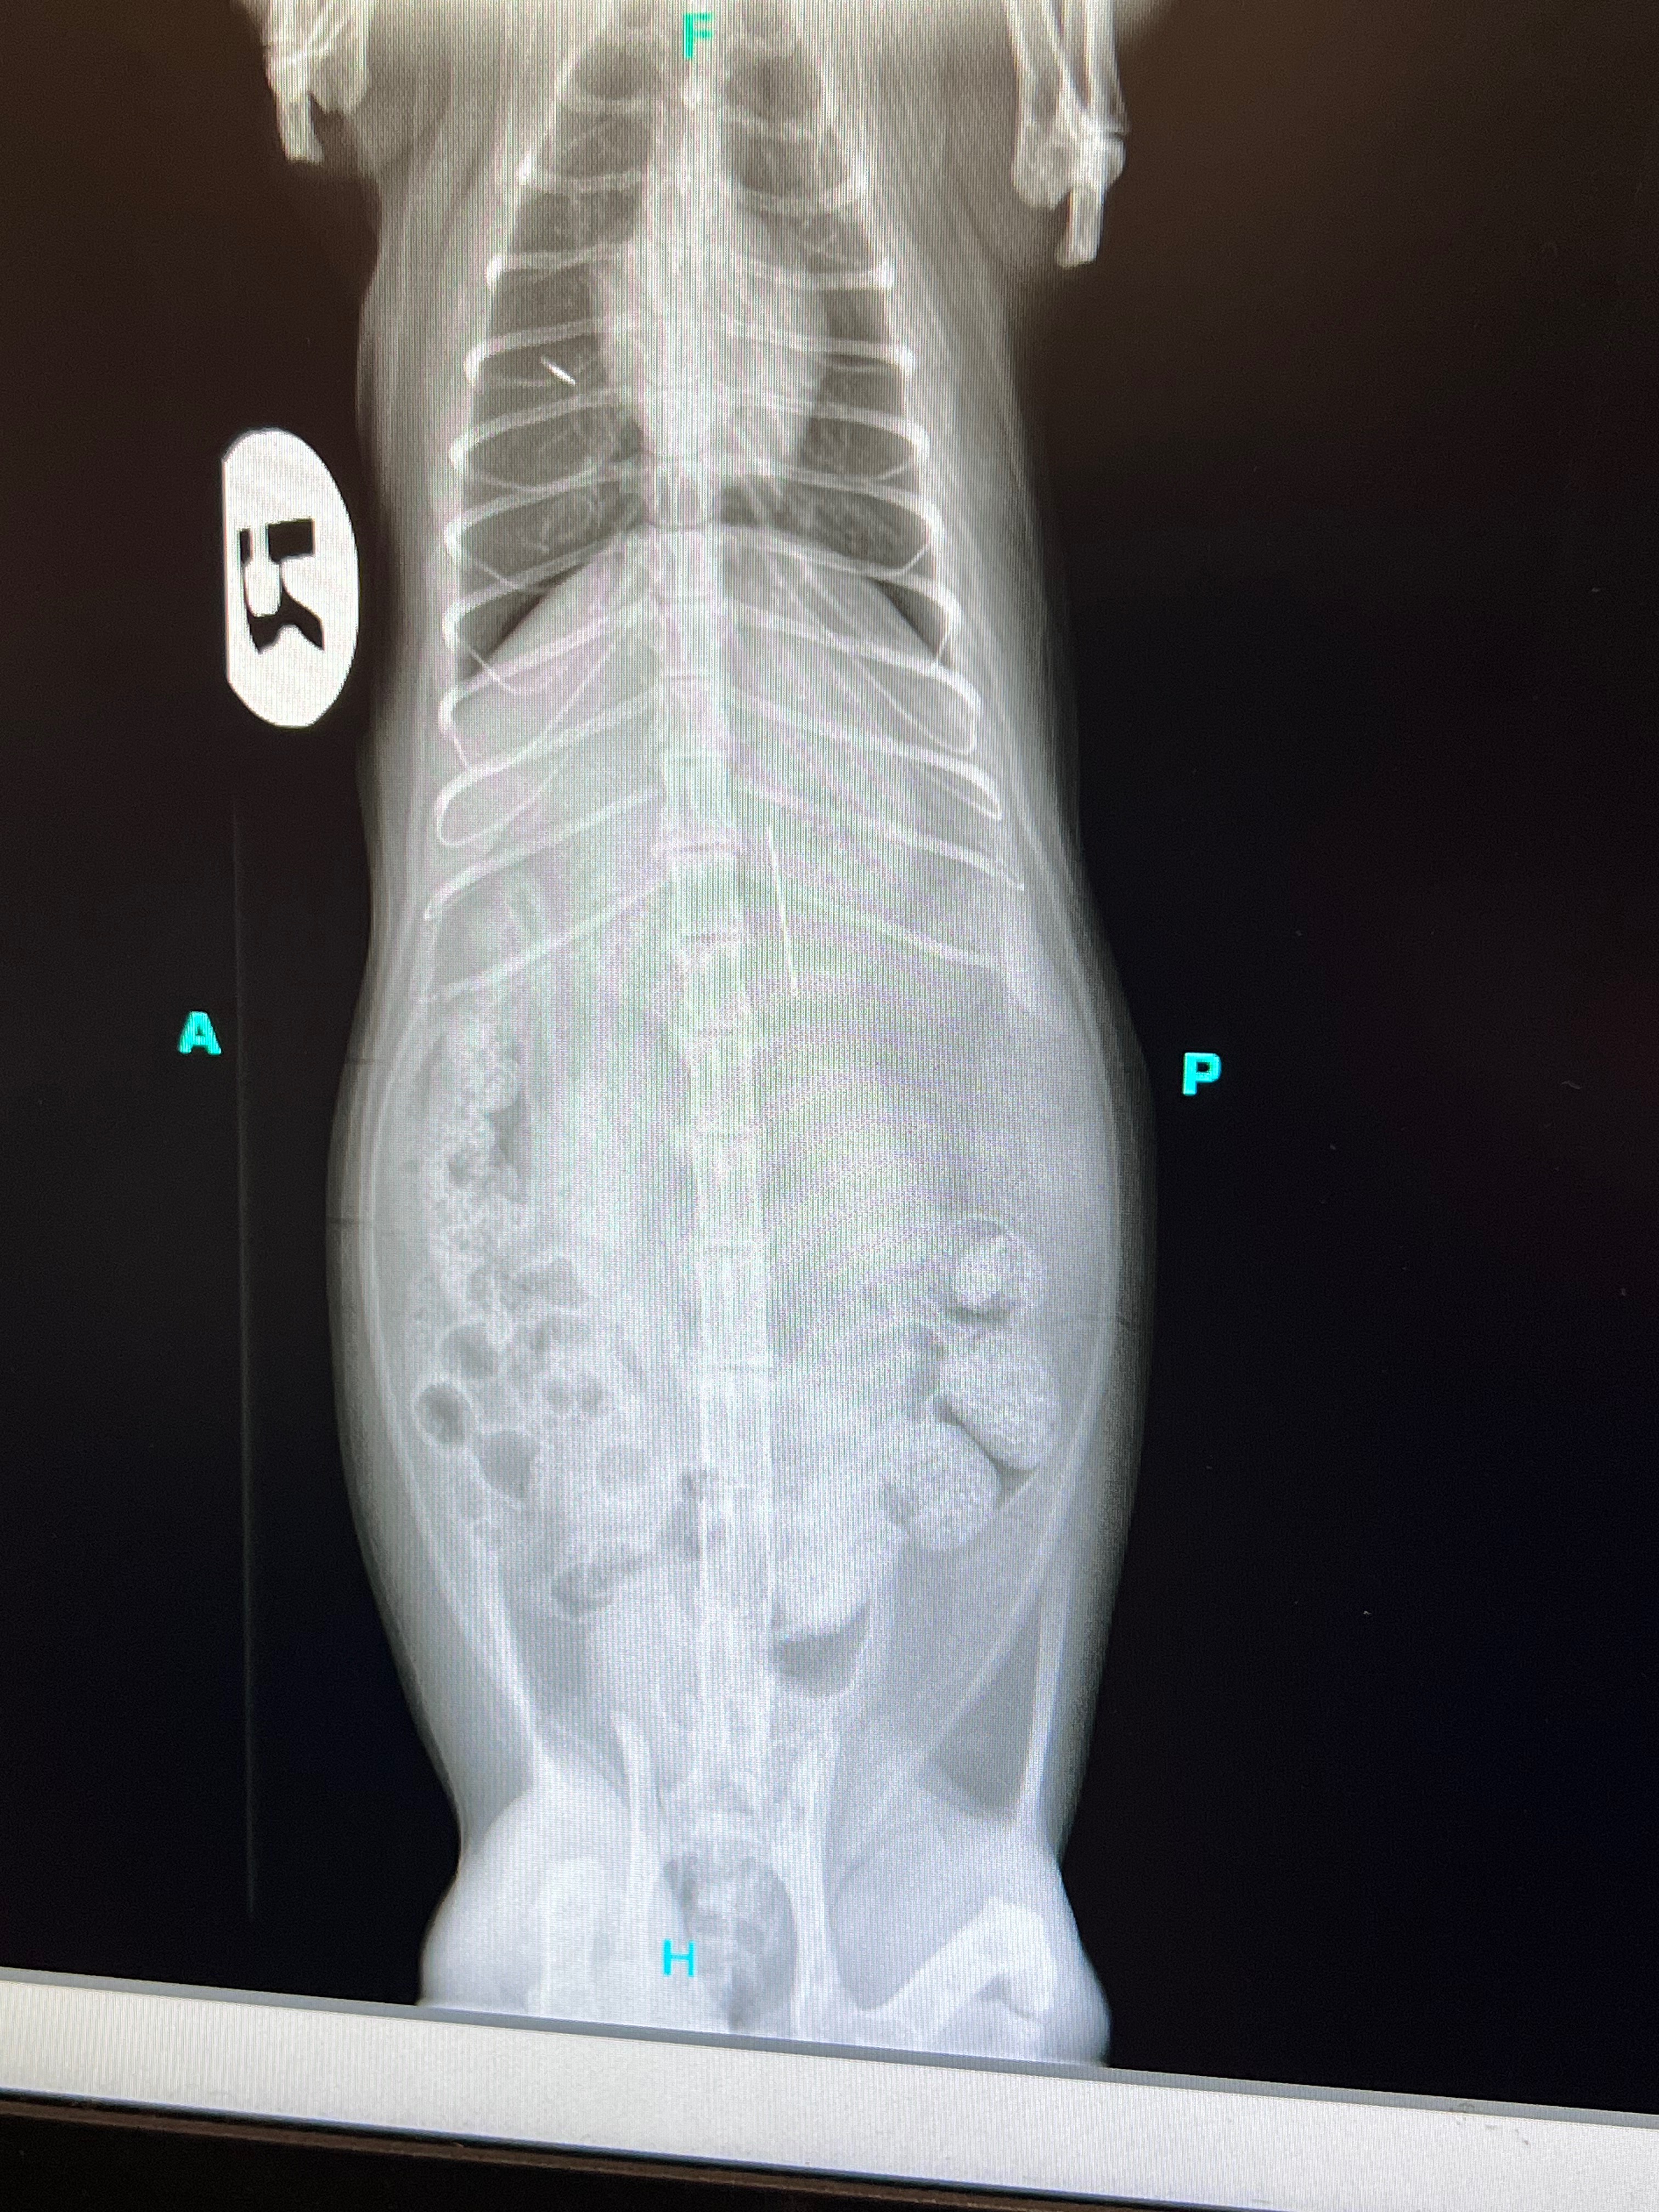

We called the nearest emergency vet in advance and were quoted with a $215 initial examination fee, we drove over and checked in. She needed to get X-rays done which were $346.50, the X-rays showed the needle was lodged at the entrance of her stomach.